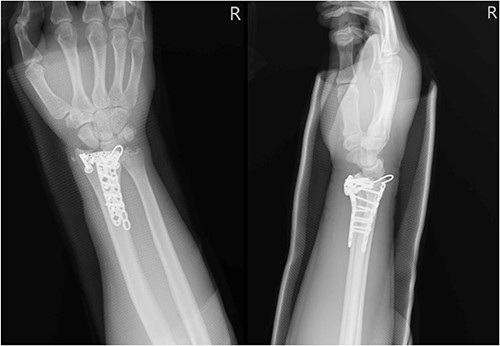

A 68-year-old female with underlying diseases of dyslipidemia, hypertension and a history of left distal radial fracture status post open reduction internal fixation on 4 April 2021, presented to our plastic surgery OPD on October 2022 with complaints of limited left thumb flexion for the past month. She reported experiencing sudden pain in her left forearm and left wrist radial site while pulling grass at home. On examination, she was found to have poor flexion of the left thumb, which was suggestive of a rupture of the FPL tendon. Left wrist X-ray showed fracture over radius with compression plate fixation (Fig. 3). After thorough discussion with the patient, it was decided that she would undergo tendon repair surgery.

Left wrist X-ray showing a fracture over the radius with compression plate fixation.

A 35-year-old male with no significant medical history fell from a third-floor balcony while working in February 2022, resulting in a right distal radius fracture that was treated with volar plate fixation. However, during an outpatient visit in November 2022, he reported a right thumb weakness that had been present for 3–4 months. Right wrist X-ray showed fracture at distal radius and carpal bones, s/p internal fixation (Fig. 5). A sonogram revealed a right thumb flexor tendon injury (Fig. 6), and he was admitted to our orthopedic ward for surgical repair of the FPL rupture on 12 November 2022. During the operation, plastic surgeon was consulted to repair the FPL rupture with a PL graft, repair the radial artery rupture and vessel with graft, repair the carpal ligament with left tensor fascia lata, release scar contracture of the volar and dorsal carpal region, and perform neurolysis of the median nerve due to adhesion to the FPL tendon.

Right wrist X-ray showing a fracture located at the distal radius and carpal bones, which was surgically treated with internal fixation.